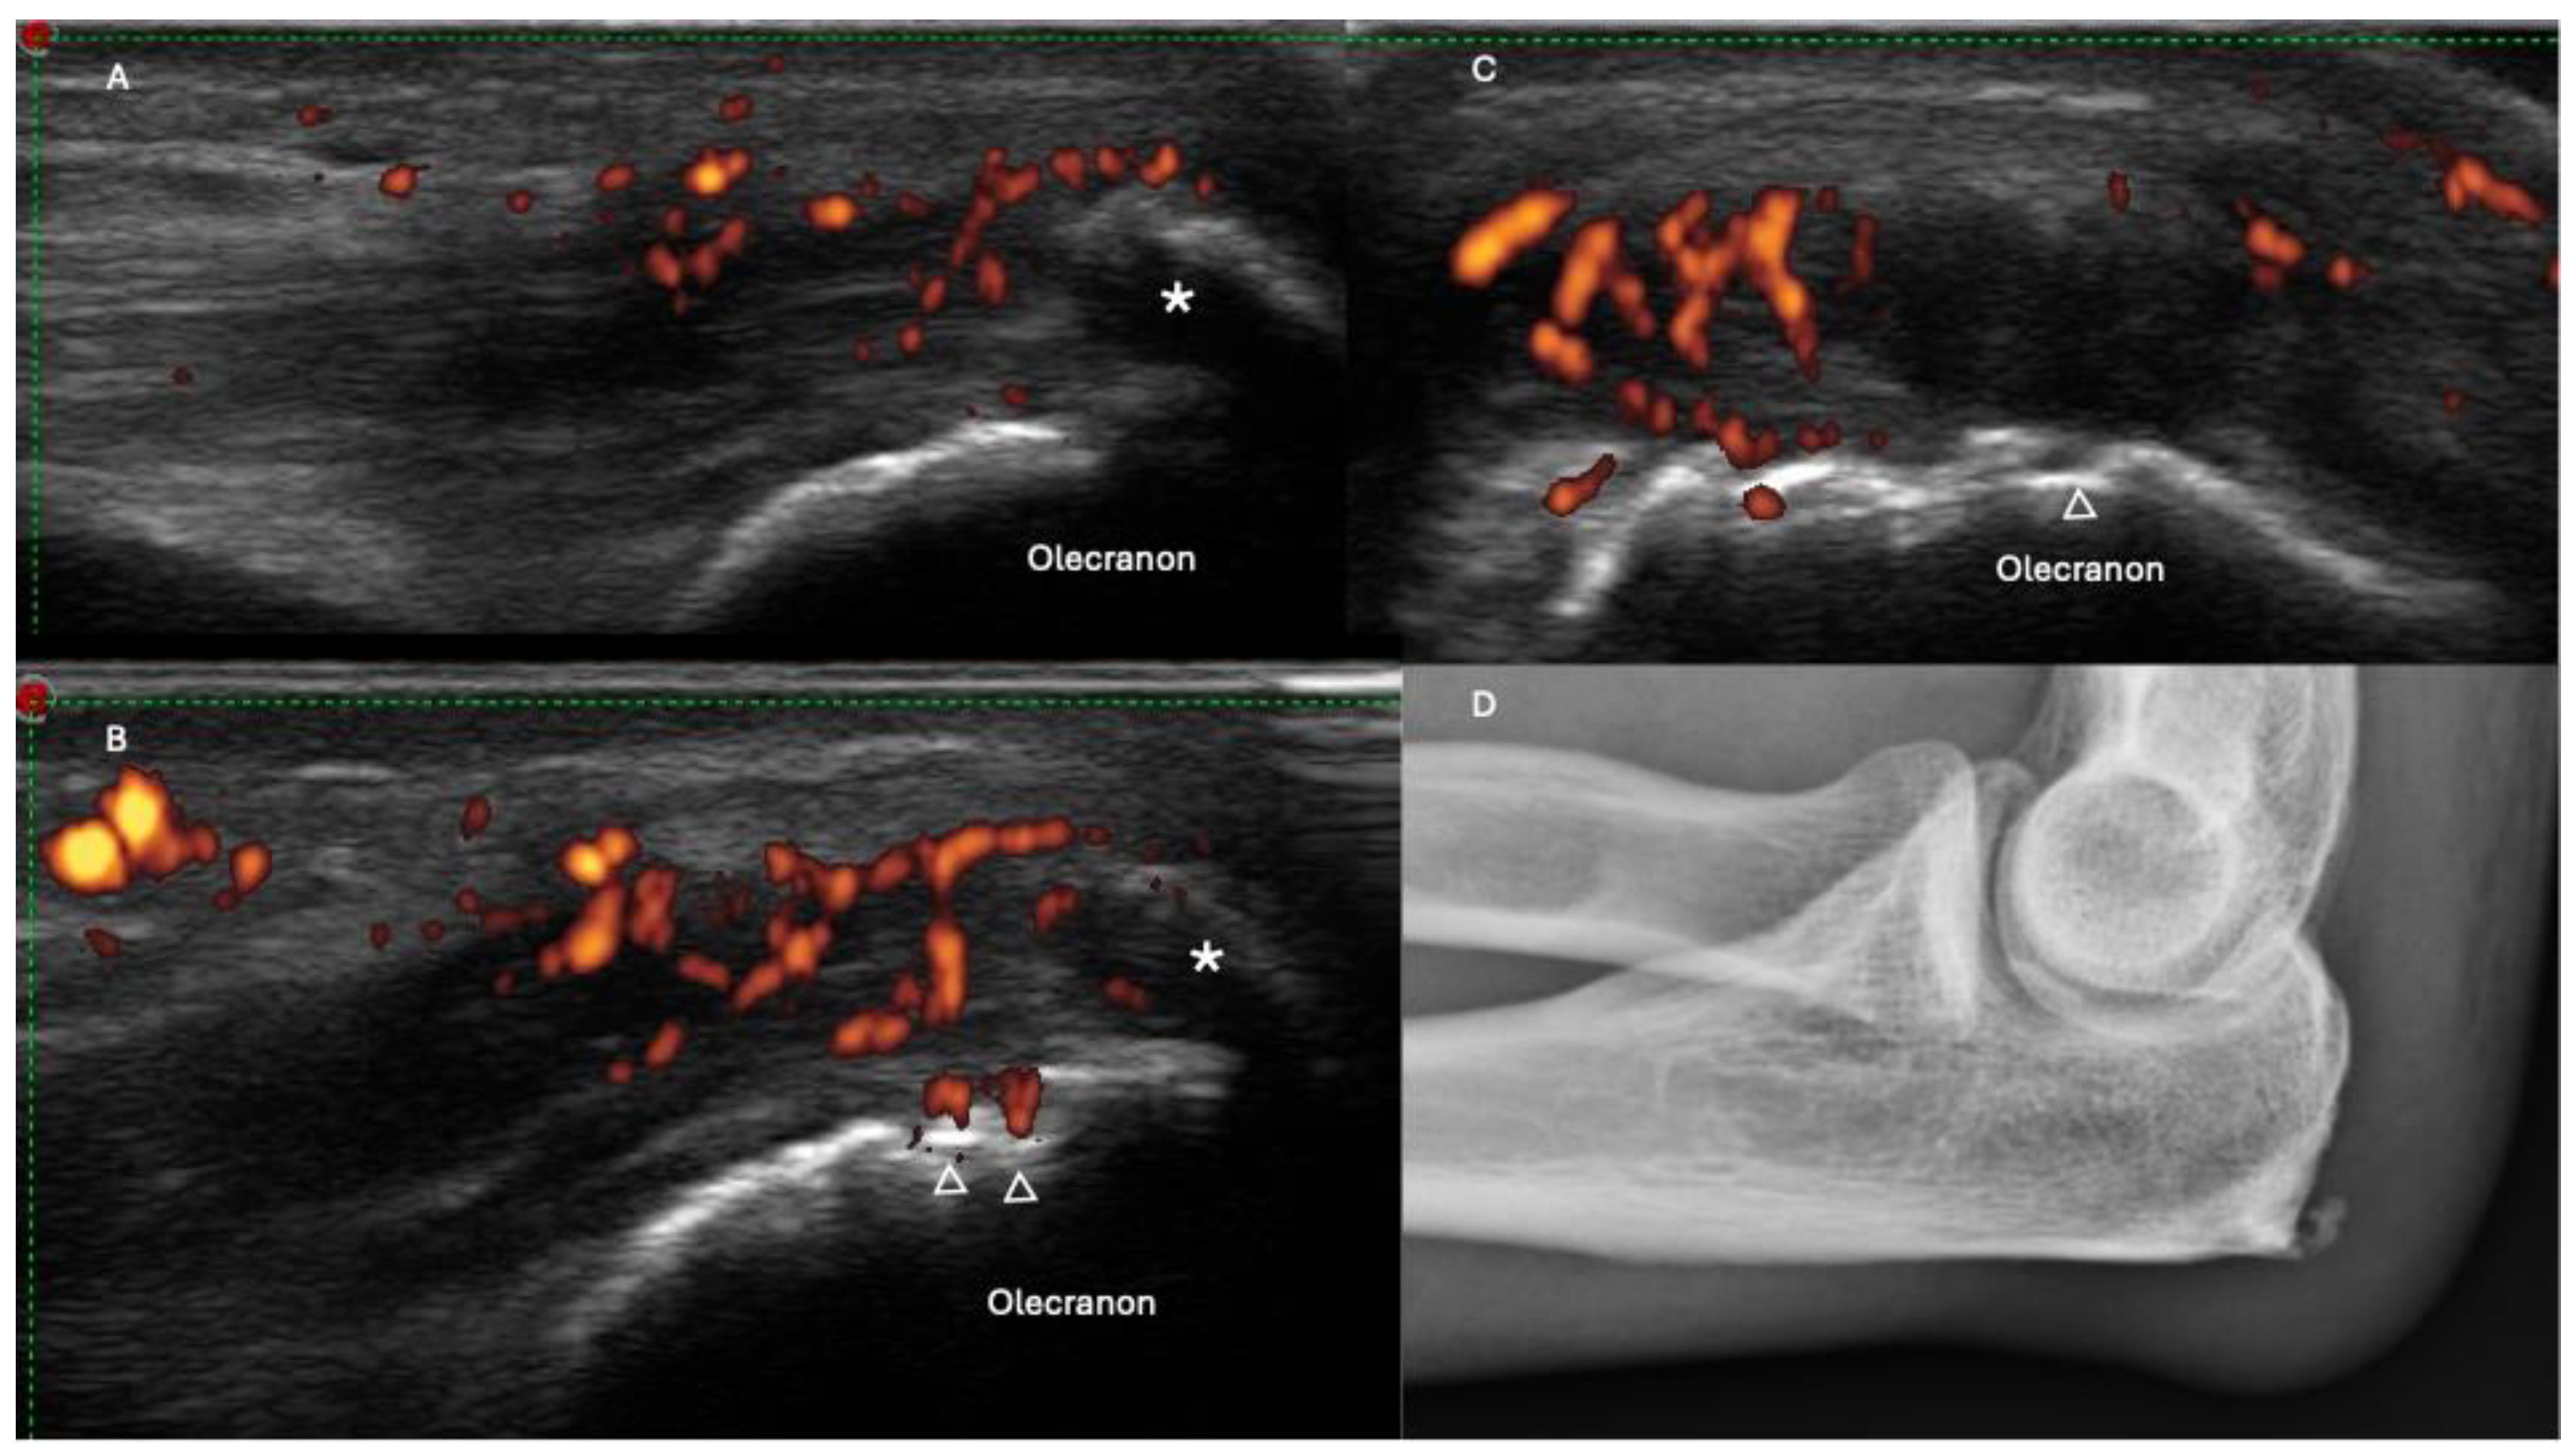

2.5. Dactylitis

- Zabotti, A.; Sakellariou, G.; Tinazzi, I.; Idolazzi, L.; Batticciotto, A.; Canzoni, M.; Carrara, G.; De Lucia, O.; Figus, F.; Girolimetto, N.; et al. Novel and reliable DACTylitis glObal Sonographic (DACTOS) score in psoriatic arthritis. Ann. Rheum. Dis. 2020, 79, 1037–1043. [Google Scholar] [CrossRef] [PubMed]

- Felbo, S.K.; Østergaard, M.; Sørensen, I.J.; Terslev, L. Which ultrasound lesions contribute to dactylitis in psoriatic arthritis and their reliability in a clinical setting. Clin. Rheumatol. 2021, 40, 1061–1067. [Google Scholar] [CrossRef]